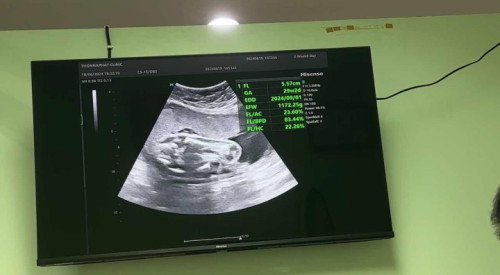

ตั้งครรภ์ 26+3w ลูก นน 1172.25g แม่ตกใจมาก เพราะเดือนที่แล้ว 22+3w ไปหาหมอน้องน้ำหนักแค่ 378g